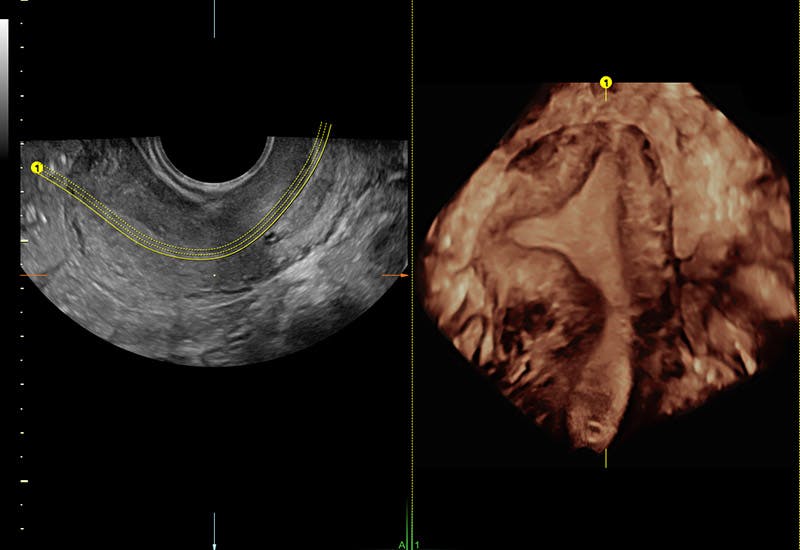

Confirmation of non-blocked fallopian tubes seen with Hysterosalpingo Contrast Sonography*.